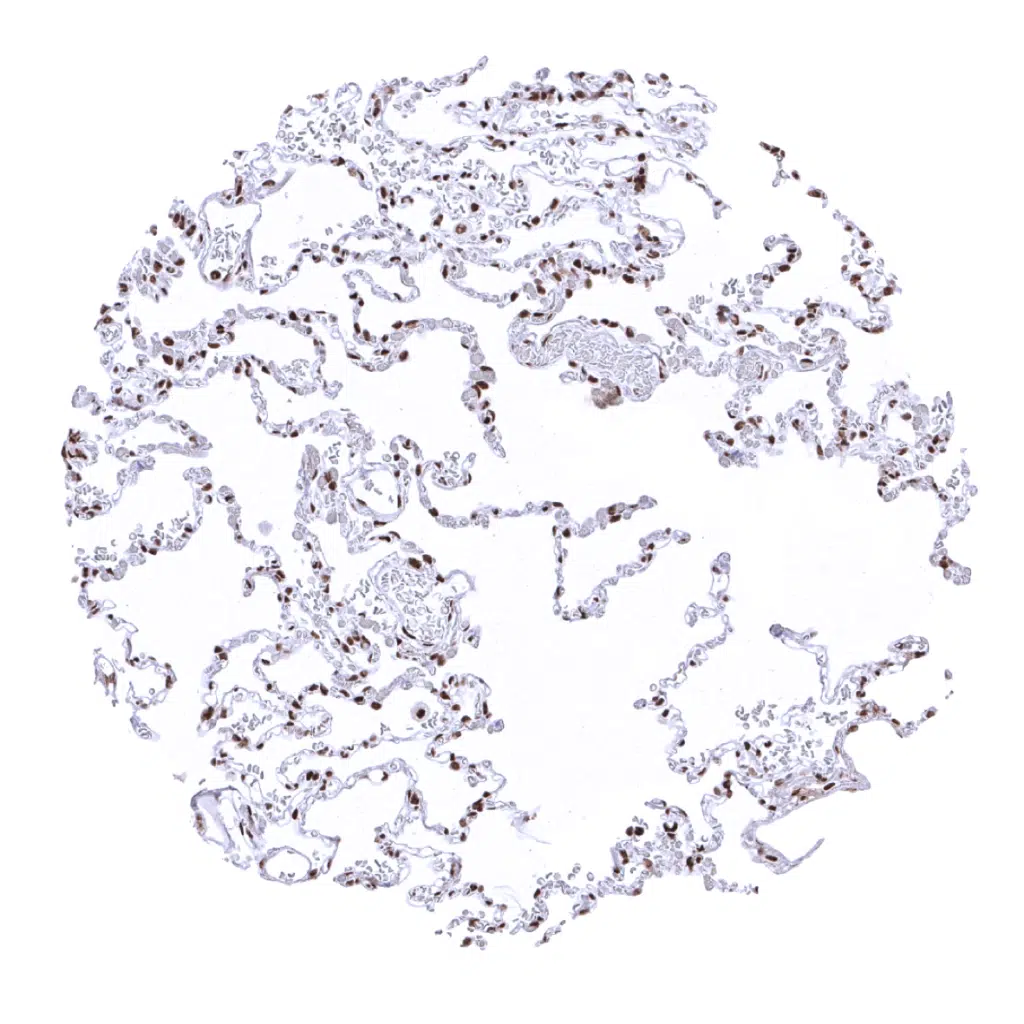

Lung